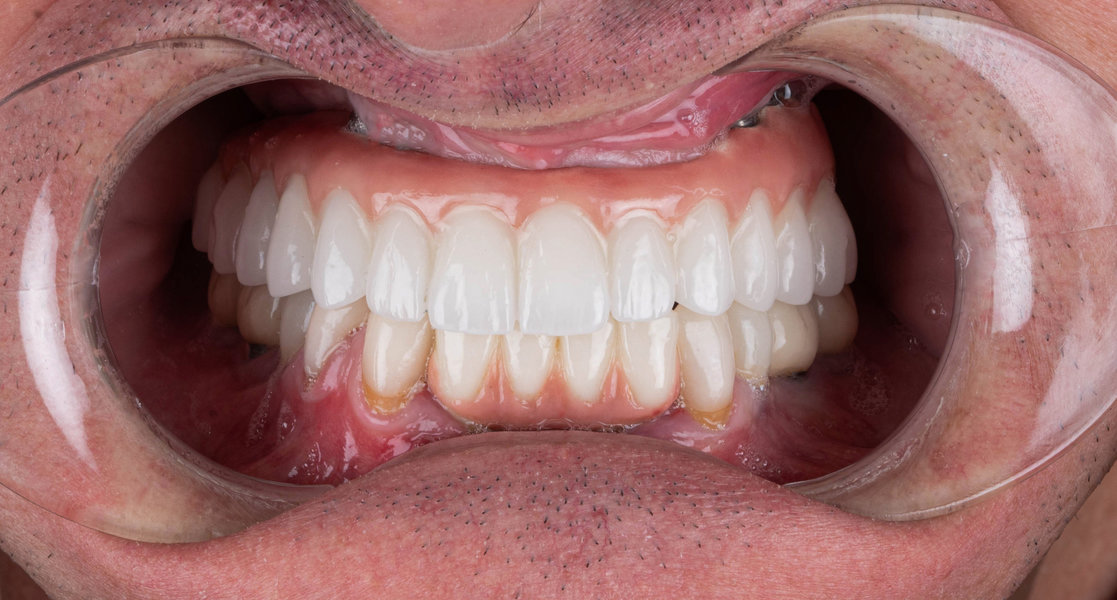

- Realizarea lucrării protetice (coroană, punte sau proteză)

- Fixarea lucrării și verificarea ocluziei

- Coroane din zirconiu sau ceramică integrală

- Proteze pe sistem de bare sau capse (All-on-4, All-on-6)

- Materiale premium – zirconiu, ceramică E-max, titan pur